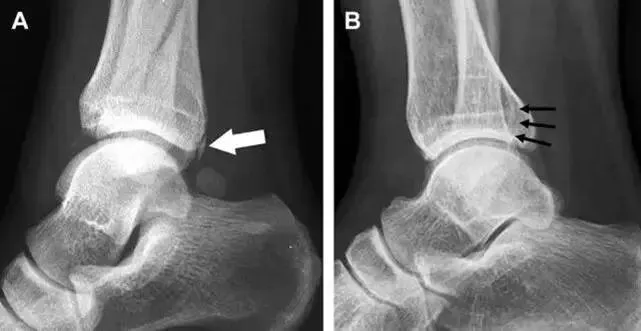

1、后踝骨折

涉及到三角韧带和外侧副韧带(LCL)的复杂性骨折常常不难发现,尤其是存在表面软组织肿胀时。然而,后胫腓韧带牵拉引起的胫骨后踝骨折则很难发现。这些骨折大小不一(如图),却很重要,因为他们常与胫骨远端螺旋骨折有关,或者是三踝骨折的一部分。

(如图)后踝骨折。A-侧位片示来源于胫骨后踝的一个小骨折碎片(箭头),因踝部扭伤导致;B-另一位跖屈损伤的患者,侧位片示一个大骨折块(箭头)。